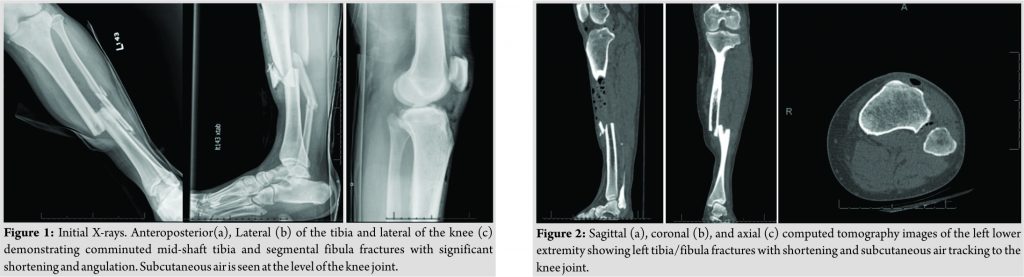

A 46-year-old male construction worker presented to the trauma bay after he was hit by a car traveling approximately 70 miles/h. The patient was stable at the time of orthopedic evaluation. Physical examination revealed tenderness along the mid-shaft of the left tibia and fibula with a 0.5-cm poke hole anteromedially and a superficial abrasion on the lateral knee. The extremity was neurovascularly intact. Radiographs (Fig. 1) and computed tomography (Fig. 2) revealed a comminuted left mid-shaft tibia and segmental fibula fractures with gas tracking throughout most of the anterior compartment, extending to the thigh and into the knee joint. In the trauma bay, the wound was irrigated with normal saline, the patient received antibiotics and tetanus vaccine, and fracture reduction followed by splinting was performed at the bedside. After informed consent was obtained, the patient underwent irrigation and debridement and open reduction and intramedullary nailing of the tibia. The PTFJ was noted to be unstable intraoperatively when manual lateral stress to the fibular head produced excessive translation laterally. Repair of the PTFJ was achieved with two suture buttons for stabilization. After surgery, the patient was placed in a knee immobilizer, started on low-molecular-weight heparin for deep vein thrombosis prophylaxis, and began physical therapy before he was discharged home on the post-operative day 3.

The patient was taken to the operating room with a plan for irrigation and debridement, intramedullary nailing of the tibia and PTFJ reduction and fixation. The patient was placed in a supine position, and the extremity was prepped and draped in a sterile fashion. The open wound was noted medially, and an ellipse-type incision was made to remove the surrounding devitalized skin and provide access to the fracture site. Further dissection revealed the saphenous vein and nerve deep into the wound. These structures were carefully retracted and protected. A curette was used to debride the bone ends, and the wound was subsequently irrigated with 9L of normal saline. The tibia was provisionally realigned using point-to-point clamps. An intramedullary nail was then placed using a suprapatellar approach. The quadricep tendon was found to be intact, and a longitudinal incision was made to obtain access to the joint. A protection sleeve was placed to the proximal tibia, and the guidewire was placed under C-arm guidance. After the guidewire position was confirmed to be adequate, a ball-tipped guidewire with a small distal bend was placed into the canal and extended to the fracture site. Reduction was performed with longitudinal traction andpoint-to-point clamps previously placed at the fracture site. After obtaining satisfactory alignment, the guidewire was further extended to a site just proximal to the physeal scar. An 8-mm cutting reamer was then used to ream the canal, followed by sequential reaming to the appropriately sized nail. The intramedullary nail was then opened and inserted to the proper depth under C-arm guidance. Anteroposterior and lateral films were once again acquired to confirm reduction. Three proximal and 2 distal locking screws were then placed. After the intramedullary nail was secured, the ankle was stressed under fluoroscopic guidance, revealing a stable distal syndesmosis and ankle joint. However, on stressing the proximal syndesmosis with a lateral stress, the proximal fibula demonstrated significant lateral translation and the PTFJ was found to be unstable. A lazy-S incision was made over the proximal fibula and dissection was made down to the PTFJ and proximal fibula, with care taken to avoid injury to the common fibular nerve. The tibiofibular interface was cleaned and a K-wire was placed to achieve proper preliminary alignment. Reduction was confirmed using anteroposterior and lateral images. Two suture buttons were placed through the proximal fibula to the tibia, and the PTFJ was noted to be stable under stress per fluoroscopic evaluation. Images were compared to the contralateral extremity, and reduction was determined to be adequate. All incisions were irrigated with normal saline, a drain was placed in the subcutaneous layer, and the deep, subcutaneous, and skin layers of all incisions were closed. A wound vacuum-assisted closure was placed over the previously ellipsed area of skin at the open portion of the fracture. The patient was then admitted to the hospital and placed in a total range of motion knee immobilizer that was unlocked 0–90°. His compartments were monitored closely postoperatively. He was instructed not to bear weight on the left lower extremity and placed on low-molecular-weight heparin for deep vein thrombosis prophylaxis, and physical therapy was started during hospitalization. He was discharged on the post-operative day 3. He began 25% weight bearing at 6 weeks. Imaging studies immediately postoperatively (Fig. 3) and at 6 months follow-up revealed stable fixation and adequate healing. At 6months, the patient had returned to work, was able to walk without support, and was using a wheelchair only for transporting long distances. At the patient’s 2-year post-operative follow-up appointment, imaging studies demonstrated complete healing of the left mid-tibial and fibular diaphysis with a well-seated intramedullary nail and syndesmotic buttons proximally without evidence of hardware loosening (Fig. 4). At this time, the patient had continued working, walked without support, had a full range of motion, and was neurovascularly intact.